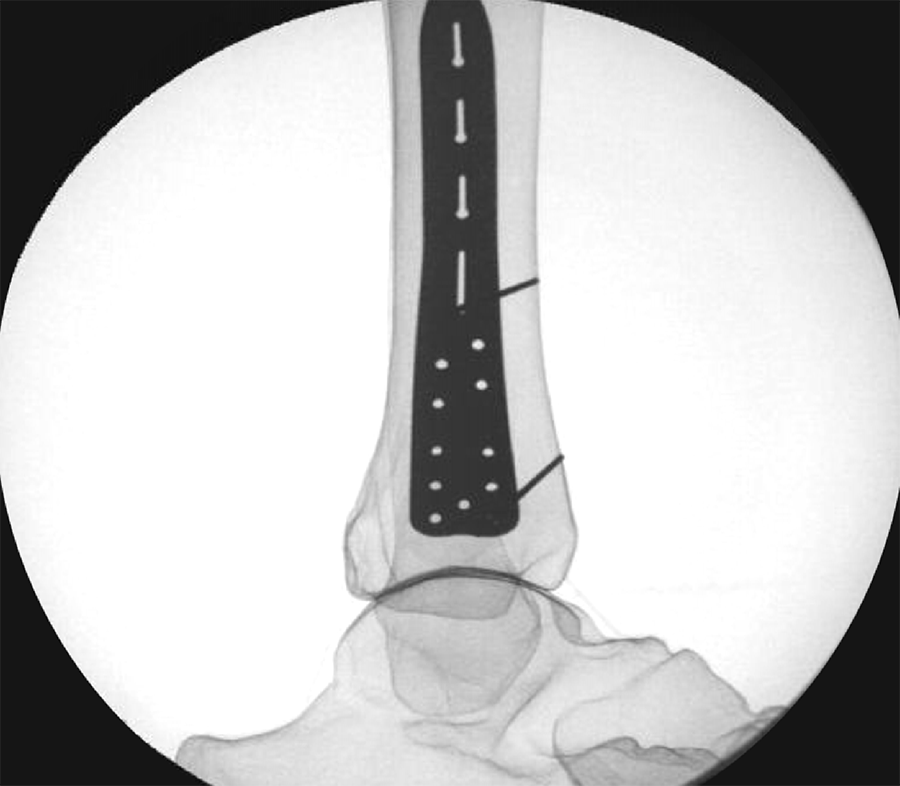

To provide an economical and effective solution, the new templates are manufactured using 3D printing technology and utilizing non-implantable stainless steel. The templates mimic the shape of the respective anatomic plates (Fig 1) and allow reprocessing for repeated use. They are radiopaque, and K-wire holes indicate the location of plate holes (Fig 2). To minimize system complexity, templates are provided for the shortest and most common length of an implant. Determination of other plate sizes can be deduced from straight measurements. The templates are labeled “DO NOT BEND” as they will no longer mimic the partnered implant, and repeated bending can result in template breakage.